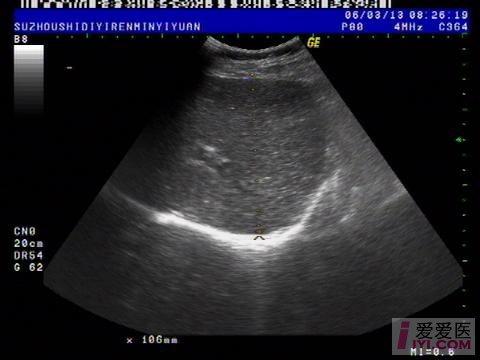

今天上午检查的一位病人, 胆囊切除术后会不会一定伴有胆总管扩张?

肝脏:左叶:长度47mm,厚度63mm 右叶:斜径106mm,形态规则,包膜完整,肝区光点细密,内部回声均匀,肝内血管走行清晰。 门静脉内径10mm。

胆囊:已切除。 胆总管:内径:11mm,胆囊窝未见积液。

1.肝未见异常。

2.胆总官扩张。